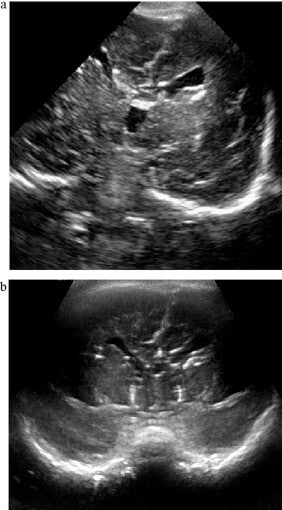

O exame inicia-se com imagens em escala de cinza pela fontanela anterior, em planos coronal e sagital: geralmente, seis a oito cortes coronais são obtidos dos lobos frontais aos occipitais, seguidos de cortes sagitais da linha média e parasagitais bilaterais.

Janelas acústicas e cortes principais

As janelas acústicas mais utilizadas na neurossonografia neonatal são:

- Fontanela anterior (a principal e mais acessível).

- Fontanela mastoidea.

- Fontanela posterior.

- Acesso transtemporal.

A fontanela anterior permite a obtenção de cortes coronais e sagitais amplos, fundamentais para o exame sistemático do encéfalo. As janelas mastoidea e transtemporal são especialmente úteis para a avaliação da fossa posterior, enquanto a fontanela posterior pode oferecer melhor visualização da região occipital e das estruturas adjacentes.